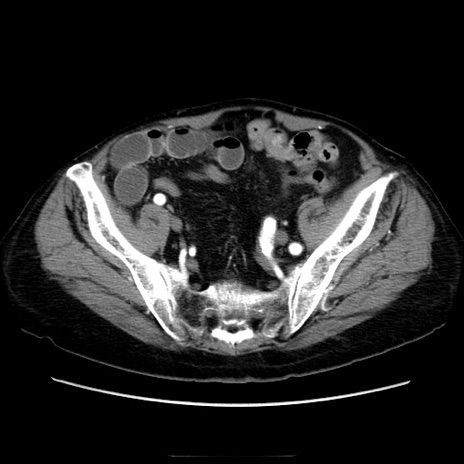

冠状断像

症例21(横断像)

【症例】70歳代男性

【主訴】腹痛

【現病歴】肝硬変・肝細胞癌にてかかりつけの方。約9時間前に食後より腹痛出現。症状が徐々に増悪し、嘔吐出現したため来院。

【既往歴】肝硬変、肝細胞癌(RFA、TACE後)

【身体所見】意識清明、表情苦悶様、BT 36℃、BP 129/78mmHg、P 88bpm、SpO2 97%(RA)、右上腹部から心窩部にかけて圧痛あり、反跳痛なし、筋性防御あり。

【データ】WBC 5800、CRP 0.16